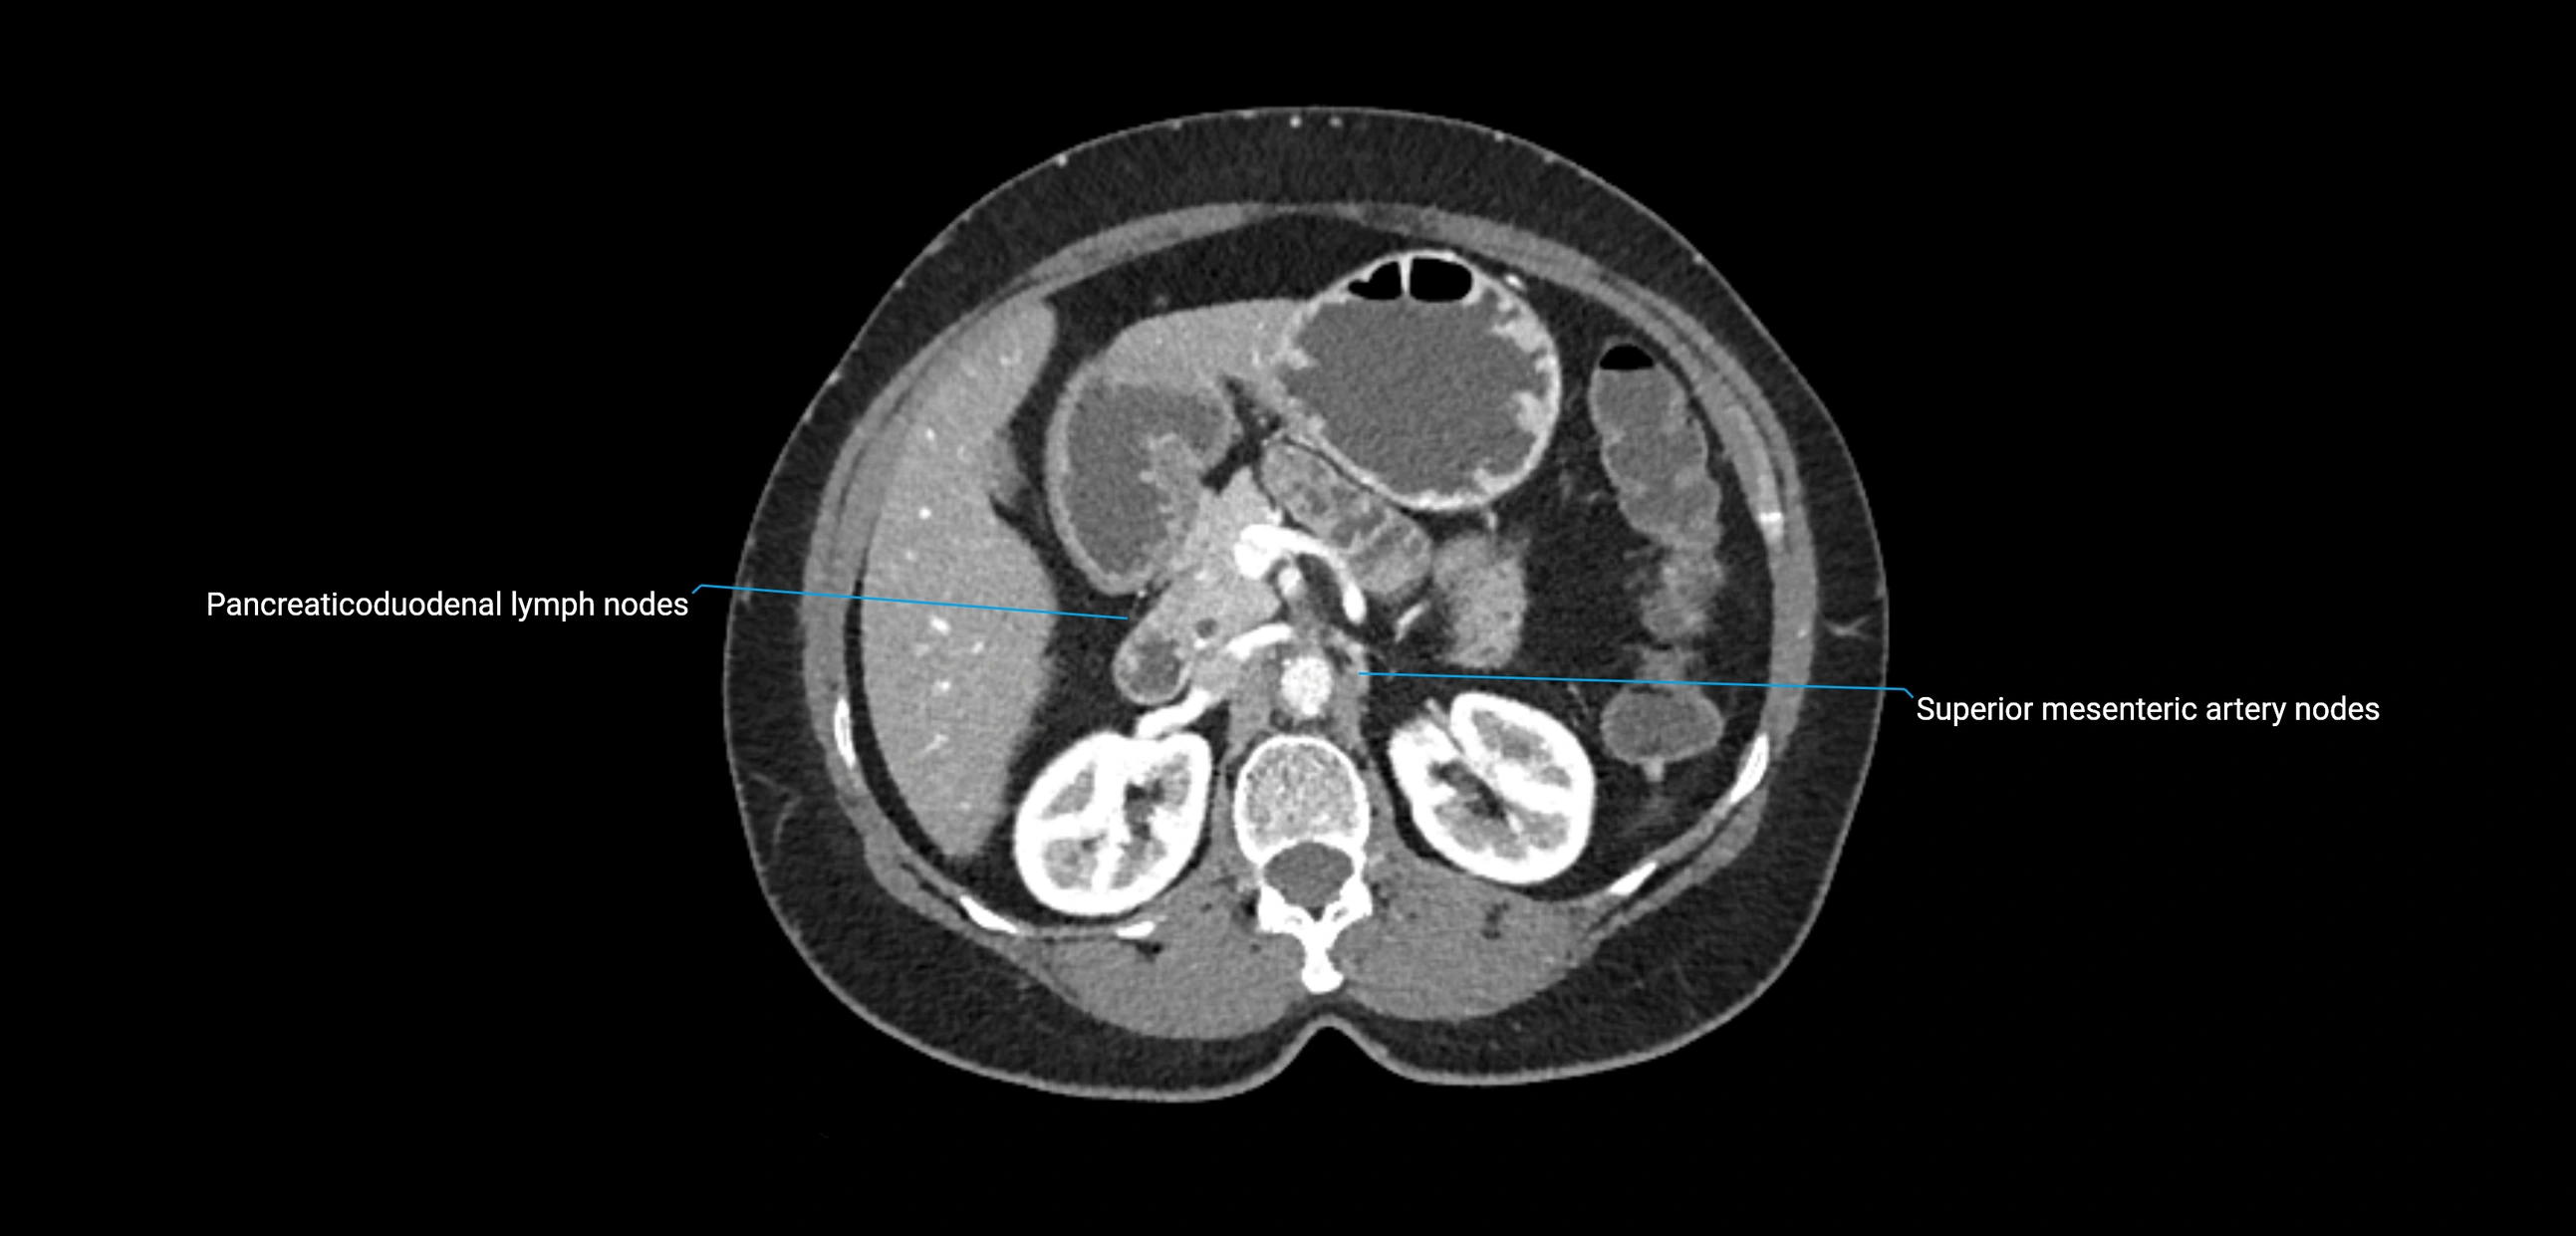

CT Appearance

CT Pre-Contrast:

• Nodes appear as soft-tissue density nodules adjacent to the aorta and IVC

• Calcification may be seen in chronic infections (e.g., tuberculosis)

CT Post-Contrast:

• Normal nodes enhance homogeneously

• Malignant nodes may show heterogeneous enhancement, central necrosis, or conglomerate formation

• Size >1 cm short axis is suspicious, though morphology and distribution are equally important

CT Venography (CTV):

• Demonstrates nodal encasement or compression of adjacent vessels (aorta, IVC, renal veins)

• Useful in staging testicular and ovarian malignancies

• Provides 3D reconstructions for retroperitoneal lymph node dissection planning

CT image

image